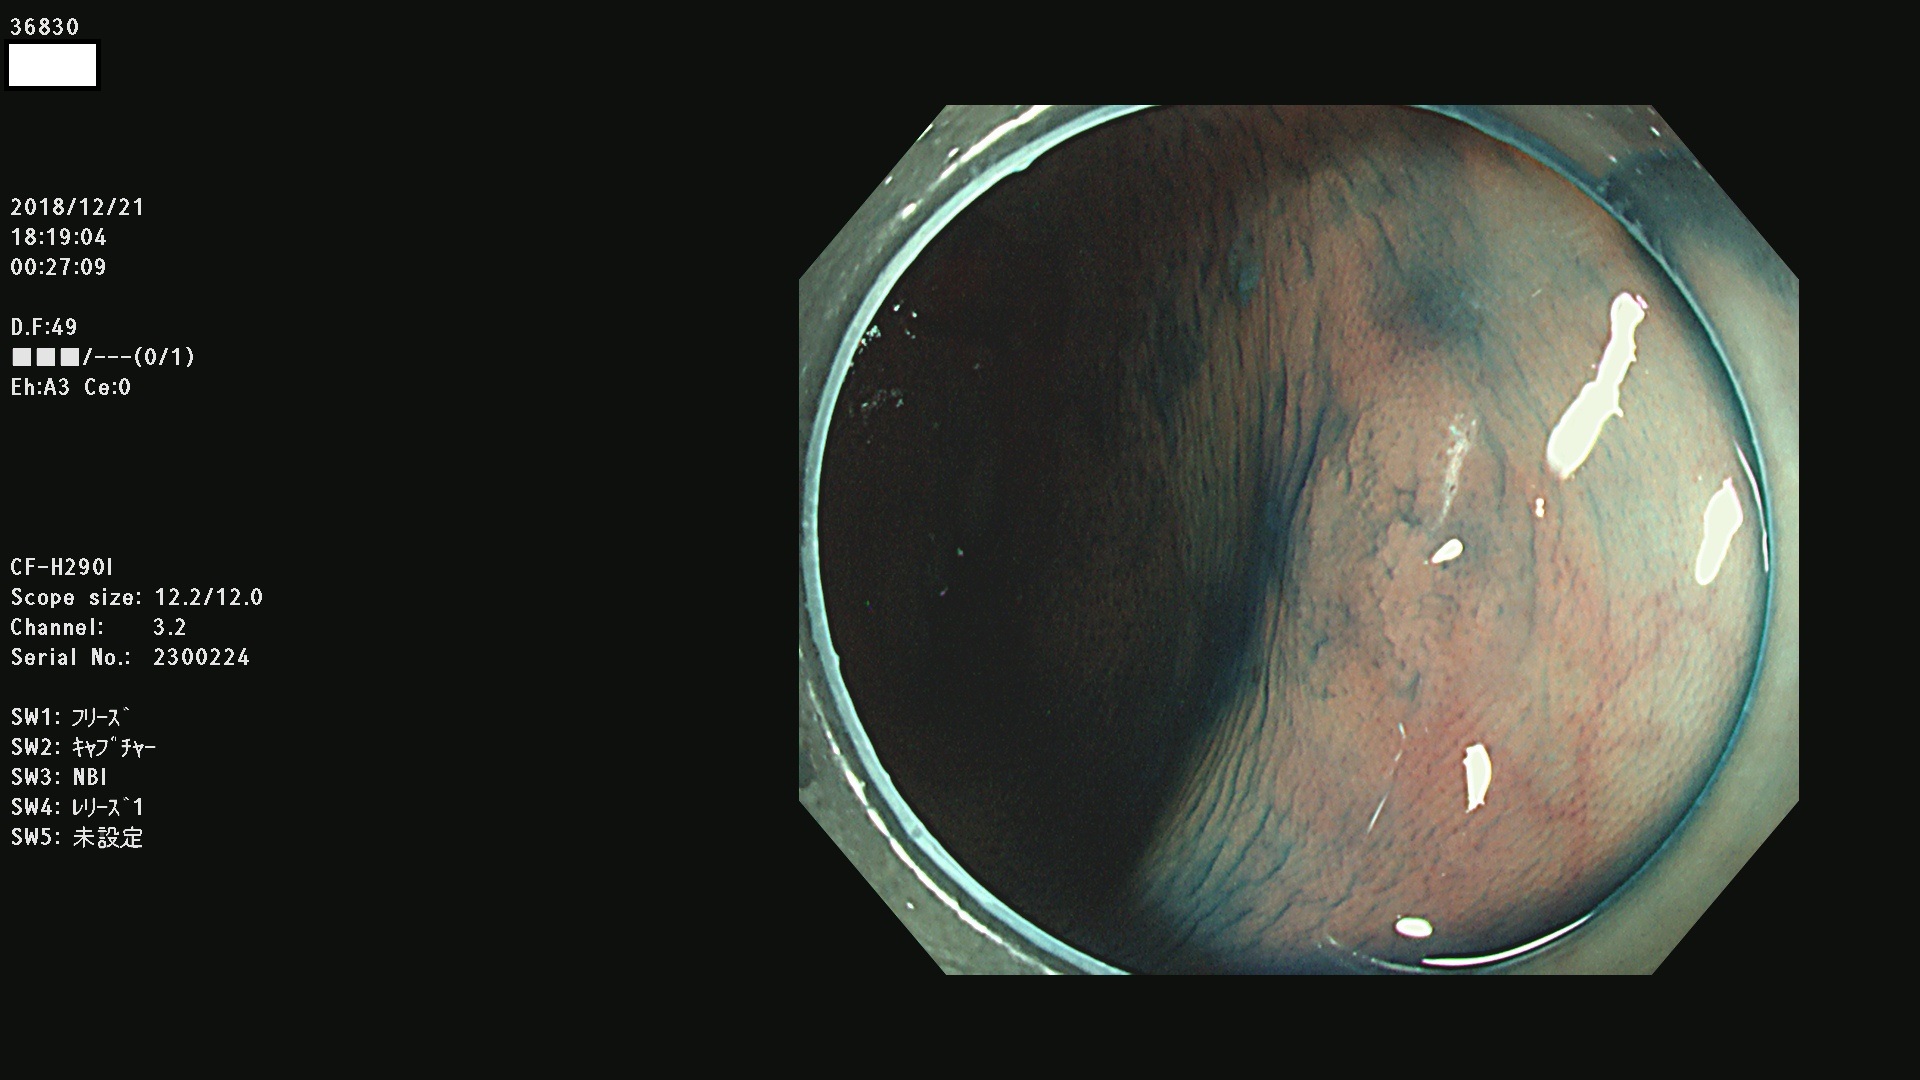

36804 36806 36807 36808 36809 36810 36811 36813 36815 36816 36817 36818 36820 36821 36822 36824 36825 36826 36828 36829 36830 36831 36832 36833 36834 36835 36837 36840 36841 36842 36845 36846 36848 36849 36851 36852 36853 36854 36855 36857 36859 36860 36861 36862(SSAPのみ) 36863 36864 36866 36868 36869 36870 36873 36875 36877 36878 36879 36881 36882 36883 36884 36885 36886 36887 36888 36889 36891 36892 36893 36894 36895 36896 36897 36898 36899

発見困難で危険性の高い平坦型病変(上記100名より抽出)